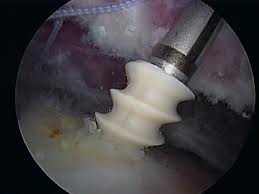

We practice open surgery but have a specialisation in arthroscopic and minimally invasive treatments for traumatic and degenerative conditions. Mr Treseder's role includes accurate diagnosis and advice, planning and supervision of rehabilitation and non operative interventions such as medications, injections and physiotherapy and planning and undertaking any required surgery. He works with an experienced team of physiotherapists, radiologists and orthotists.

Conditions Mr Treseder treats frequently include fractures and dislocations of the upper limb and lower limb, deformity correction, joint problems and arthritis.